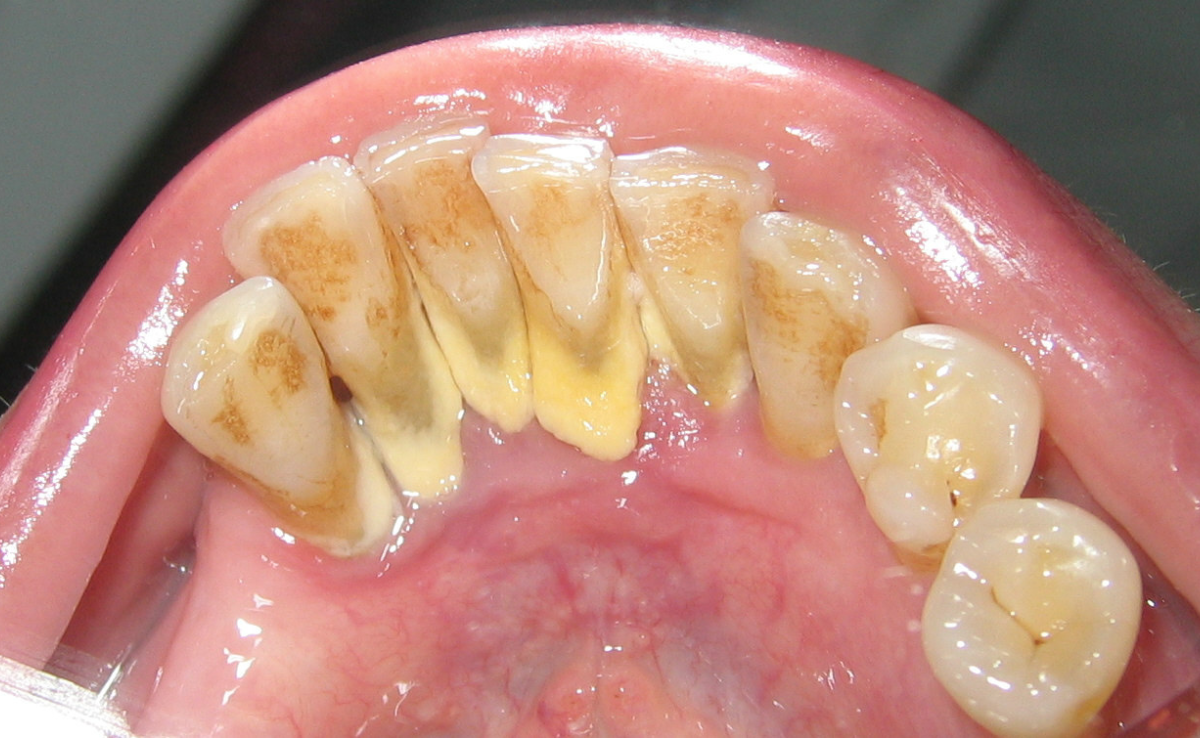

Plak ialah lapisan lembut yang melekat pada permukaan gigi selepas anda makan atau minum, terutama makanan bergula atau berkanji. Plak ini mengandungi bakteria yang boleh menghasilkan asid dan merosakkan enamel gigi. Jika plak tidak dibersihkan dengan betul setiap hari melalui teknik memberus dan flos yang betul, ia akan mula mengeras kerana tindak balas dengan mineral dalam air liur — dan inilah yang dinamakan karang gigi

Karang gigi yang tidak dibuang boleh bertukar warna dari kuning ke coklat atau hitam bergantung kepada tabiat harian dan pemakanan seseorang.

1. Gigi Kelihatan Kotor atau Kekuningan

Salah satu petanda awal ialah perubahan warna pada gigi. Jika anda perasan ada lapisan keras kekuningan atau coklat gelap yang tidak hilang walaupun selepas memberus, itu mungkin bukan sekadar kotoran biasa — ia adalah karang gigi.